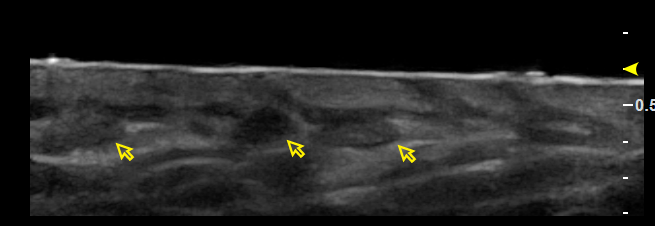

消退期血管瘤